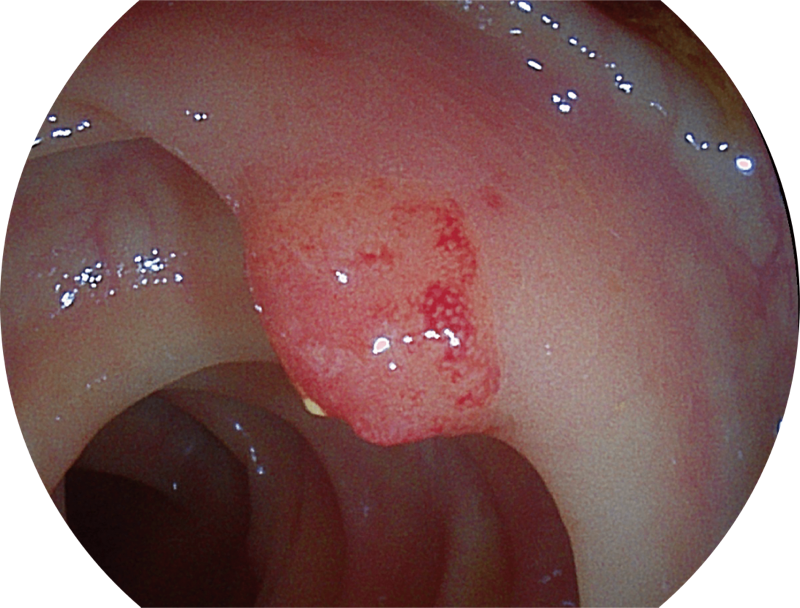

SFI图像

SFI图像

(Versatile Intelligent Staining Technology)

能够凸显黏膜浅层血管轮廓和黏膜表面微结构,适用于中、近景观察下的早癌精确诊断。